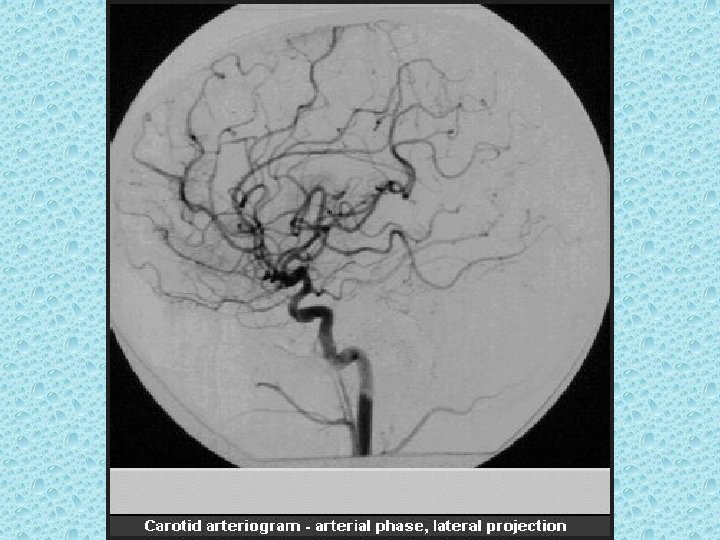

KAFA İÇİNİ BESLEYEN ARTERLER • Bilateral karotid sistem: İnternal karotid arter - A. oftalmika, a. kommunikans posterior, a. koroidea, a. serebri anterior ve media • Vertebrobaziler sistem: Vertebral arterler ve baziller arterlerden oluşur - A. Serebellaris posterior inferior (pica), anterior inferior (aica), a. serebellaris superior, a. serebri posterior

WILLIS POLİGONU • • • Bilateral internal karotid arter Bilateral anterior serebral arter Anterior kommunikan arter Bilateral post. Kommunikan arter Bilateral post serebral arter